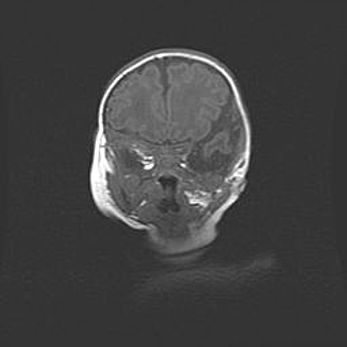

Аномалия Денди-Уокера. Признаки гипоплазии мозолистого тела.

Возраст: 5 месяцев 3 дня

Вес: 5550 г

Пол: мужской

Окружность головы: 39 см

Срок гестации: 40 недель

Аномалия Денди-Уокера – это порок развития головного мозга, для которого характерна триада симптомов: гипотрофия или аплазия червя мозжечка и/или полушарий мозжечка, расширение четвёртого желудочка с формированием ликворной кисты задней черепной ямки, гипертензионная гидроцефалия различной степени.

Гипоплазия мозолистого тела относится к дефектам внутриутробного этапа развития мозговой ткани, возникающим в процессе закладки структур головного мозга, что происходит на начальных этапах развития эмбриона.